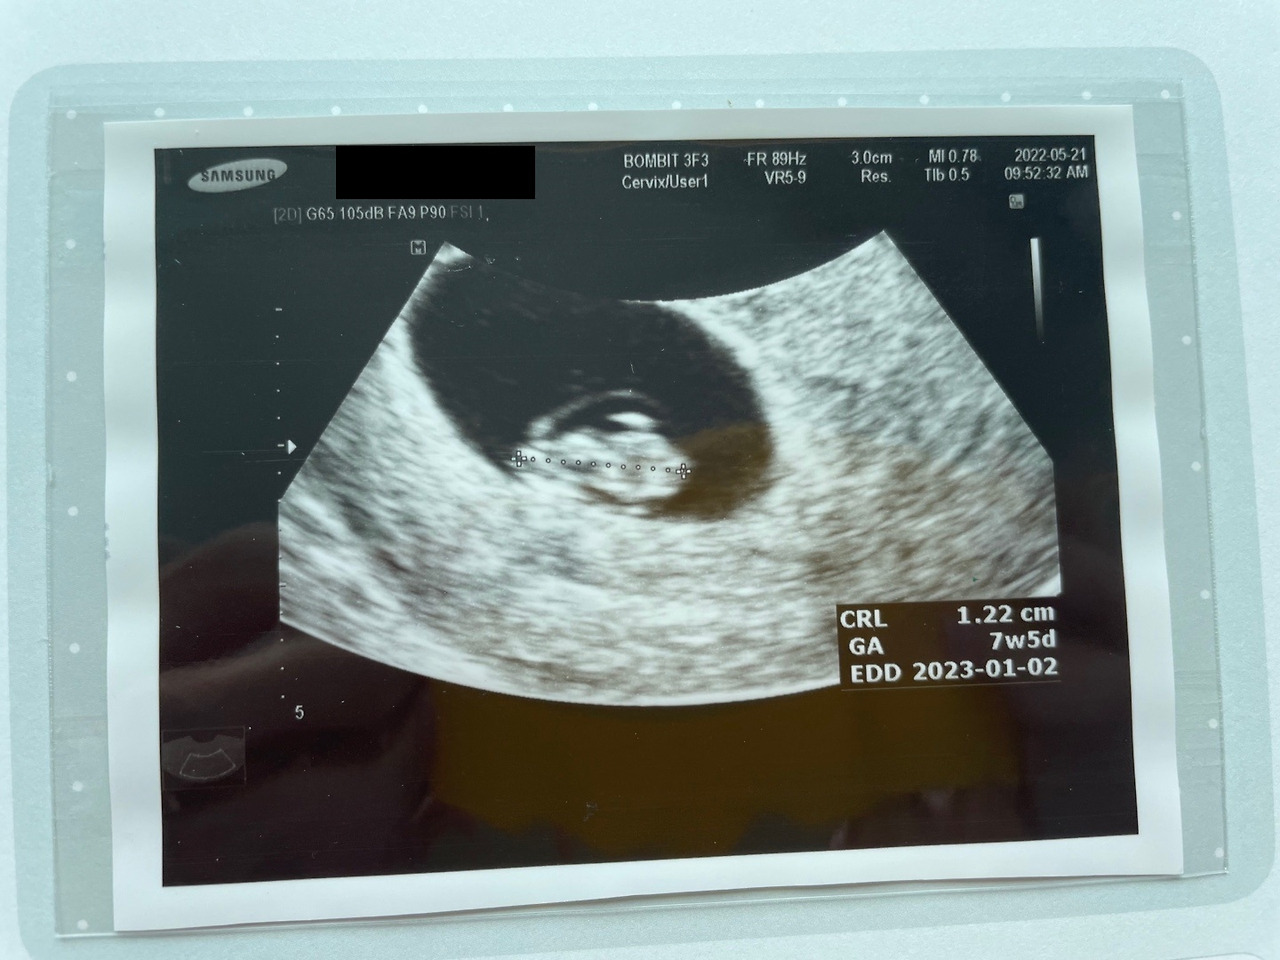

조금 대기한 뒤, 의사 선생님을 뵙고 초음파를 봤다. 오늘도 질초음파였다. 이전보다 확실히 커진 아기집과 그 안에는 아직은 꼬리가 달린듯한 올챙이 같은 아기가 있었다. 그리고 가운데에는 반짝반짝 빛나는 아기의 심장이 있었다. 초음파를 보고 난 후 보호자인 남편과 함께 진료실로 이동했다.

아이의 크기로 분만예정일 및 주수를 계산하는데, 7주 5일로 주수가 바뀌었고, 주수는 다음 주의 아기 크기로 정확히 정해진다.

아기의 크기, 모양, 심박수 모두 정상이다.

피고임이 조금 보이나 (초음파 상으로 아기집 주변 어두운 부분), 크게 걱정할 정도는 아니며, 예방 차원에서 질정을 처방해 줄 테니 2주간 사용하고 변화를 보자.

KakaoTalk_20220527_205840916.jpg 왼쪽부터 머리, 몸통, 엉덩이. 1.22cm가 된 써니